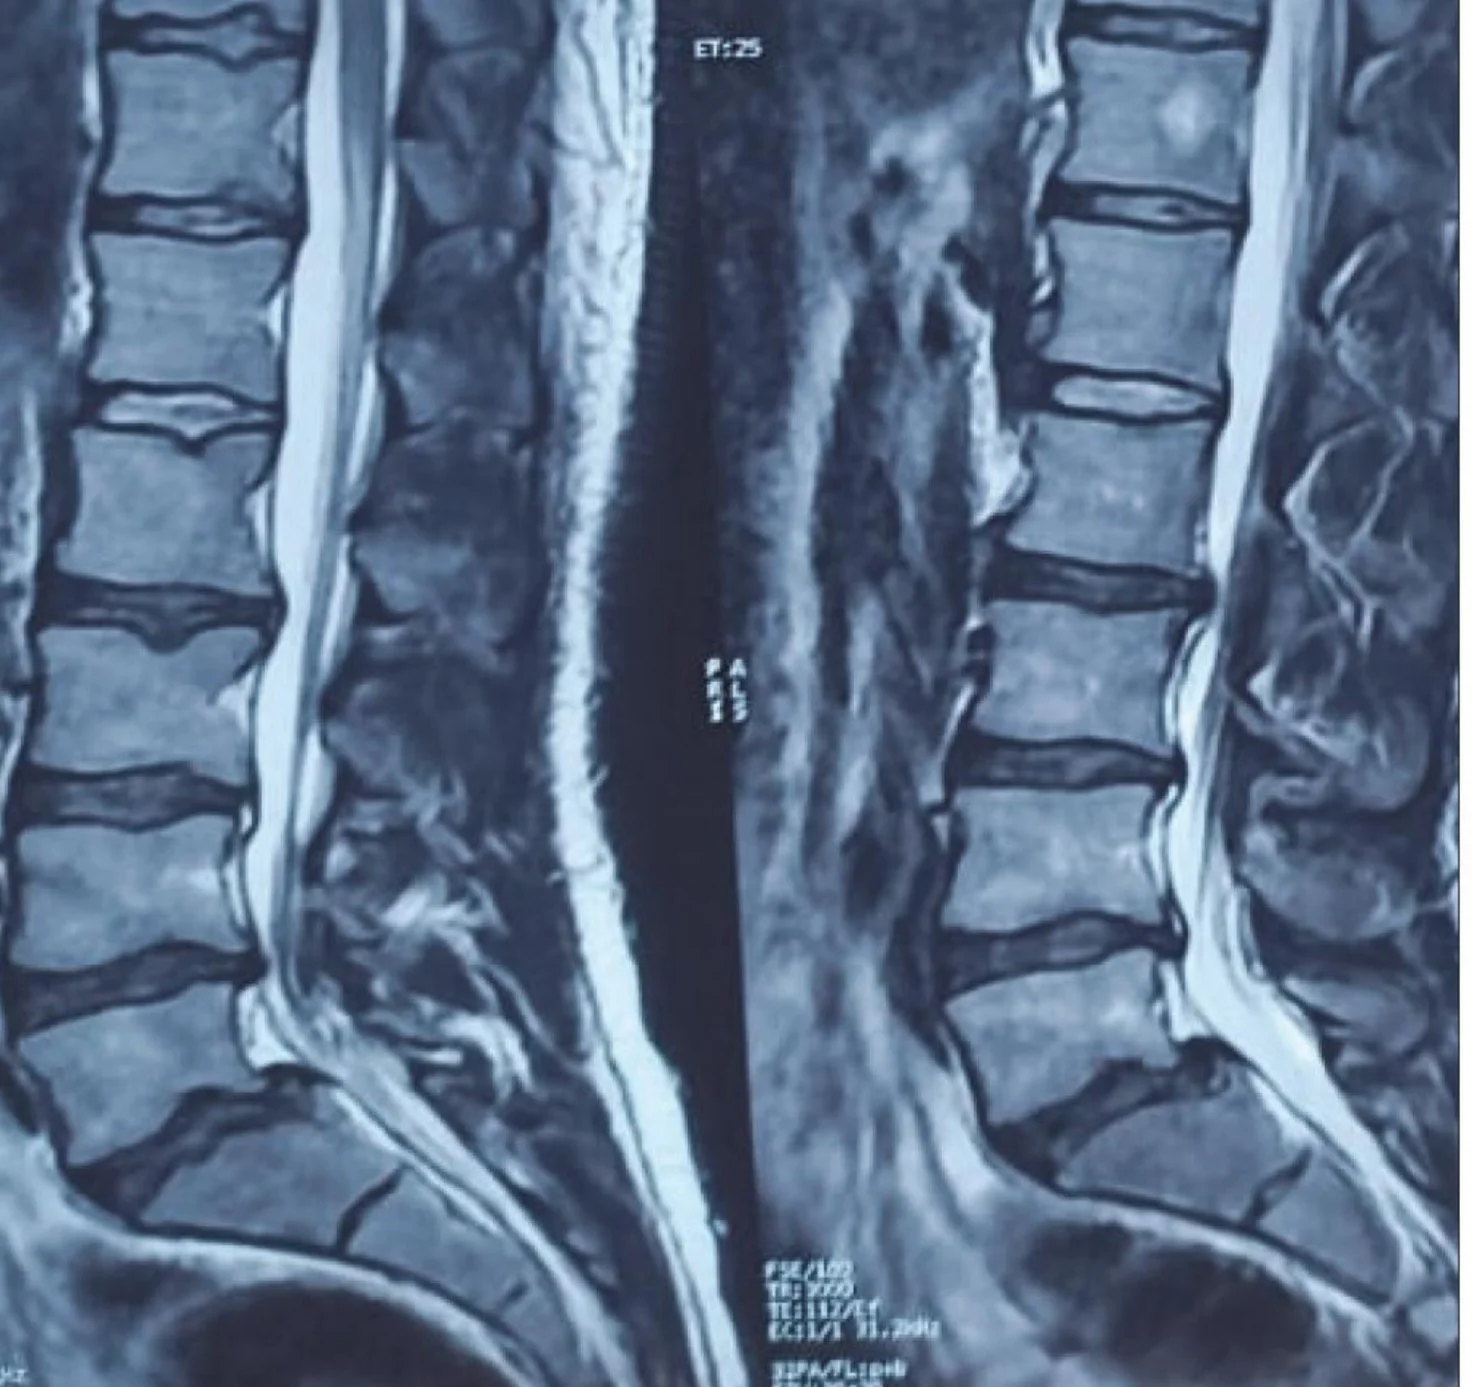

• Patients: 90 adults (mean age: 44 years; 54% male) with MRI-confirmed lumbar herniated nucleus pulposus (HNP) presenting with back and leg pain

Each patient had lumbar spine MRI and radiographs. Coronal balance parameters were measured, including the lumbosacral angle and Fractional Lumbosacral Curve (FLSC)  .